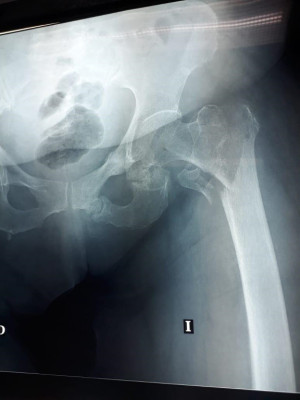

Imágenes de ortopedia y traumatología

Envíado por Dr. José Israel Flores Hernández